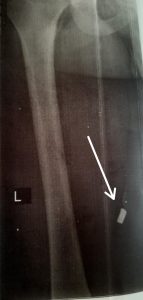

Şikayətçinin sözlərinə görə, onun sənədlərini TƏBİB-ə göndəriblər, oradan isə deyilib ki, müalicəyə ehtiyacı var. İ. Rəhimov isə iddia edir ki, onun müalicəyə ehtiyacı yoxdur. Sol əlində iki barmağının fəaliyyəti tamam dayanıb, bir barmağı əsir, ayağında isə qəlpə var.

“Sənədlərimi yazıb göndərdim Mərkəzi Hərbi Klinik Hospitala. Hospitalda baxılıb deyildi ki, barmaqları əməliyyat etsək də, fəaliyyəti bərpa olunmayacaq. Ondan sonra müalicələr dayandı, əməliyyat olunmadı. Ayağımda olan qəlpəni də çıxarmırlar, deyirlər ki, çıxarsaq ola bilər ayaq fəaliyyətini itirər. Yeriyəndə həm ağrıyır, həm də axsayıram. İndi əlillik dərəcəsi almaq istəyirəm, amma heç kim bir söz demir”.